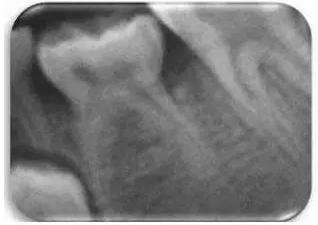

發(fā)育不全被定義為乳磨牙分叉下方的骨嵴沒有鈣化的跡象。采用Demirjian方法將相應(yīng)的前磨牙發(fā)育分為8個(gè)階段。對(duì)應(yīng)牙齒發(fā)育缺失的“0期”已被作者另外考慮(圖2)。

文獻(xiàn)直達(dá)|一項(xiàng)西班牙的研究:低位乳磨牙的發(fā)生頻率、程度、牙根吸收和前磨牙發(fā)育不全情況\

圖2 影像學(xué)觀察到的由左側(cè)第二乳磨牙的低牙合導(dǎo)致的前磨牙發(fā)育不全。